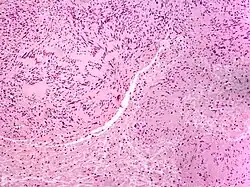

Solitary circumscribed neuroma